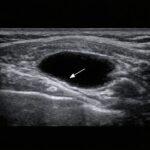

レントゲンの「変形」と痛みは一致しない

現在の研究では、

レントゲンの変形と痛みは必ずしも一致しない

ことが知られています。

実際、膝の画像所見は

症状とあまり相関しないことが多い

と報告されています。